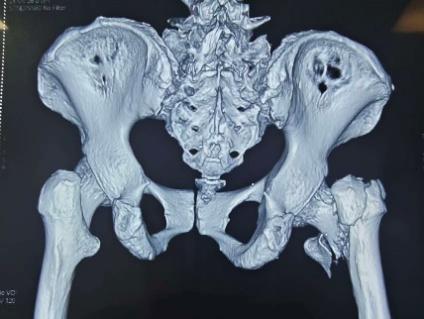

第一次内固定术后X线片及CT

此次入院前X线片及CT